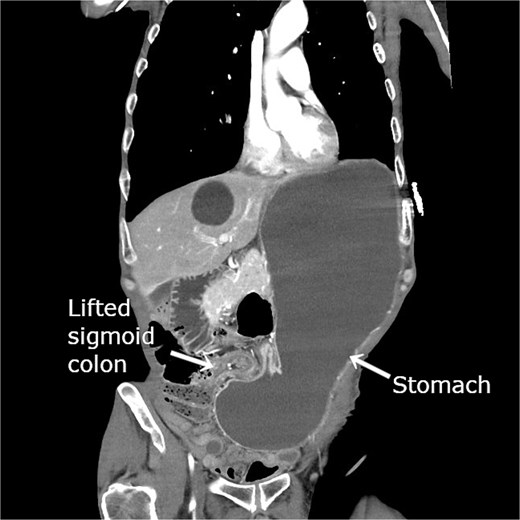

He was hemodynamically stable on admission. Laboratory test results revealed leukocytosis (white blood cells, 12 600/μL), elevated C-reactive protein level (2.99 mg/dL), and elevated blood urea nitrogen level (29.7 mg/dL). Contrast-enhanced computed tomography (CT) revealed gastric herniation through the lateral defect between the lifted sigmoid colon and the abdominal wall, causing narrowing near the antrum and marked gastric distension (Fig. 1). Gastric wall enhancement was preserved. Bilateral lung ground-glass opacities and consolidation suggested aspiration pneumonia.

Contrast-enhanced CT revealing gastric herniation through the lateral defect between the lifted sigmoid colon and abdominal wall. The elevated sigmoid colon created for colostomy compresses the pyloric region from the patient’s right side, causing focal narrowing near the antrum. Marked gastric dilatation with significant fluid retention is evident.